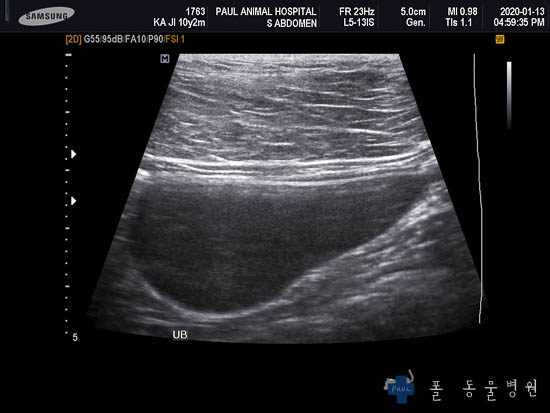

다음은 복부의 장기를 더 자세히 평가할 수 있는 초음파 검사 결과입니다.